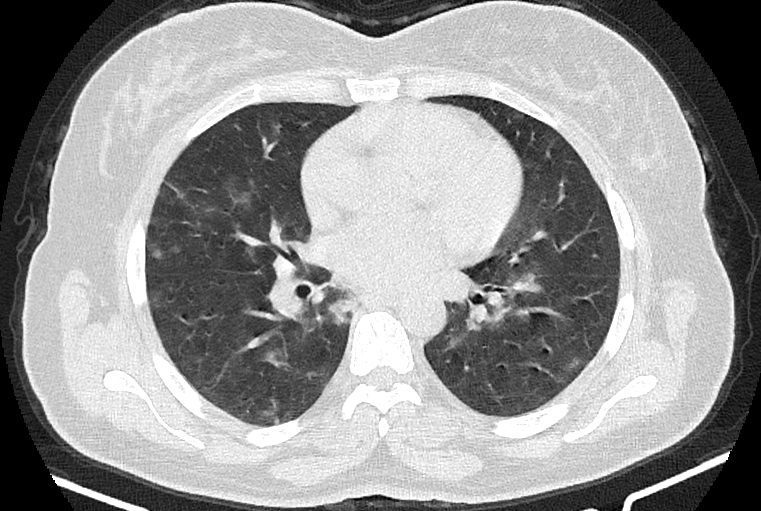

در HRCT از ريه ها(اسپيرال ، مولتي ديتکتور 16، مقاطع اگزيال با ضخامت 1mm بدون فاصله ) ، بدون كنتراست تزريقي :

-Ground glass opacities Patchy پراکنده در ريه ها مشهود است که مطرح کننده Viral pneumonia مي باشد . ( با درگيري 20 درصد حجم ريه )

نتیجه : Highly suggestive of COVID-19